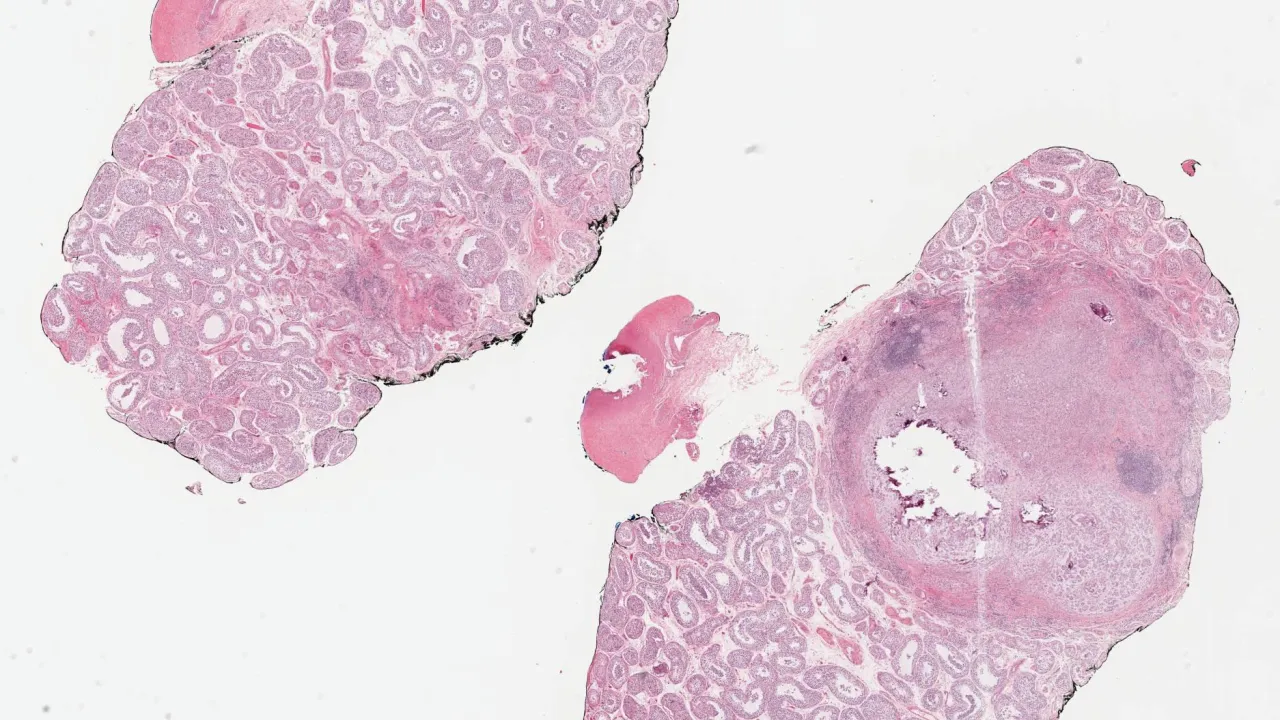

Kidney, Clear cell renal cell carcinoma